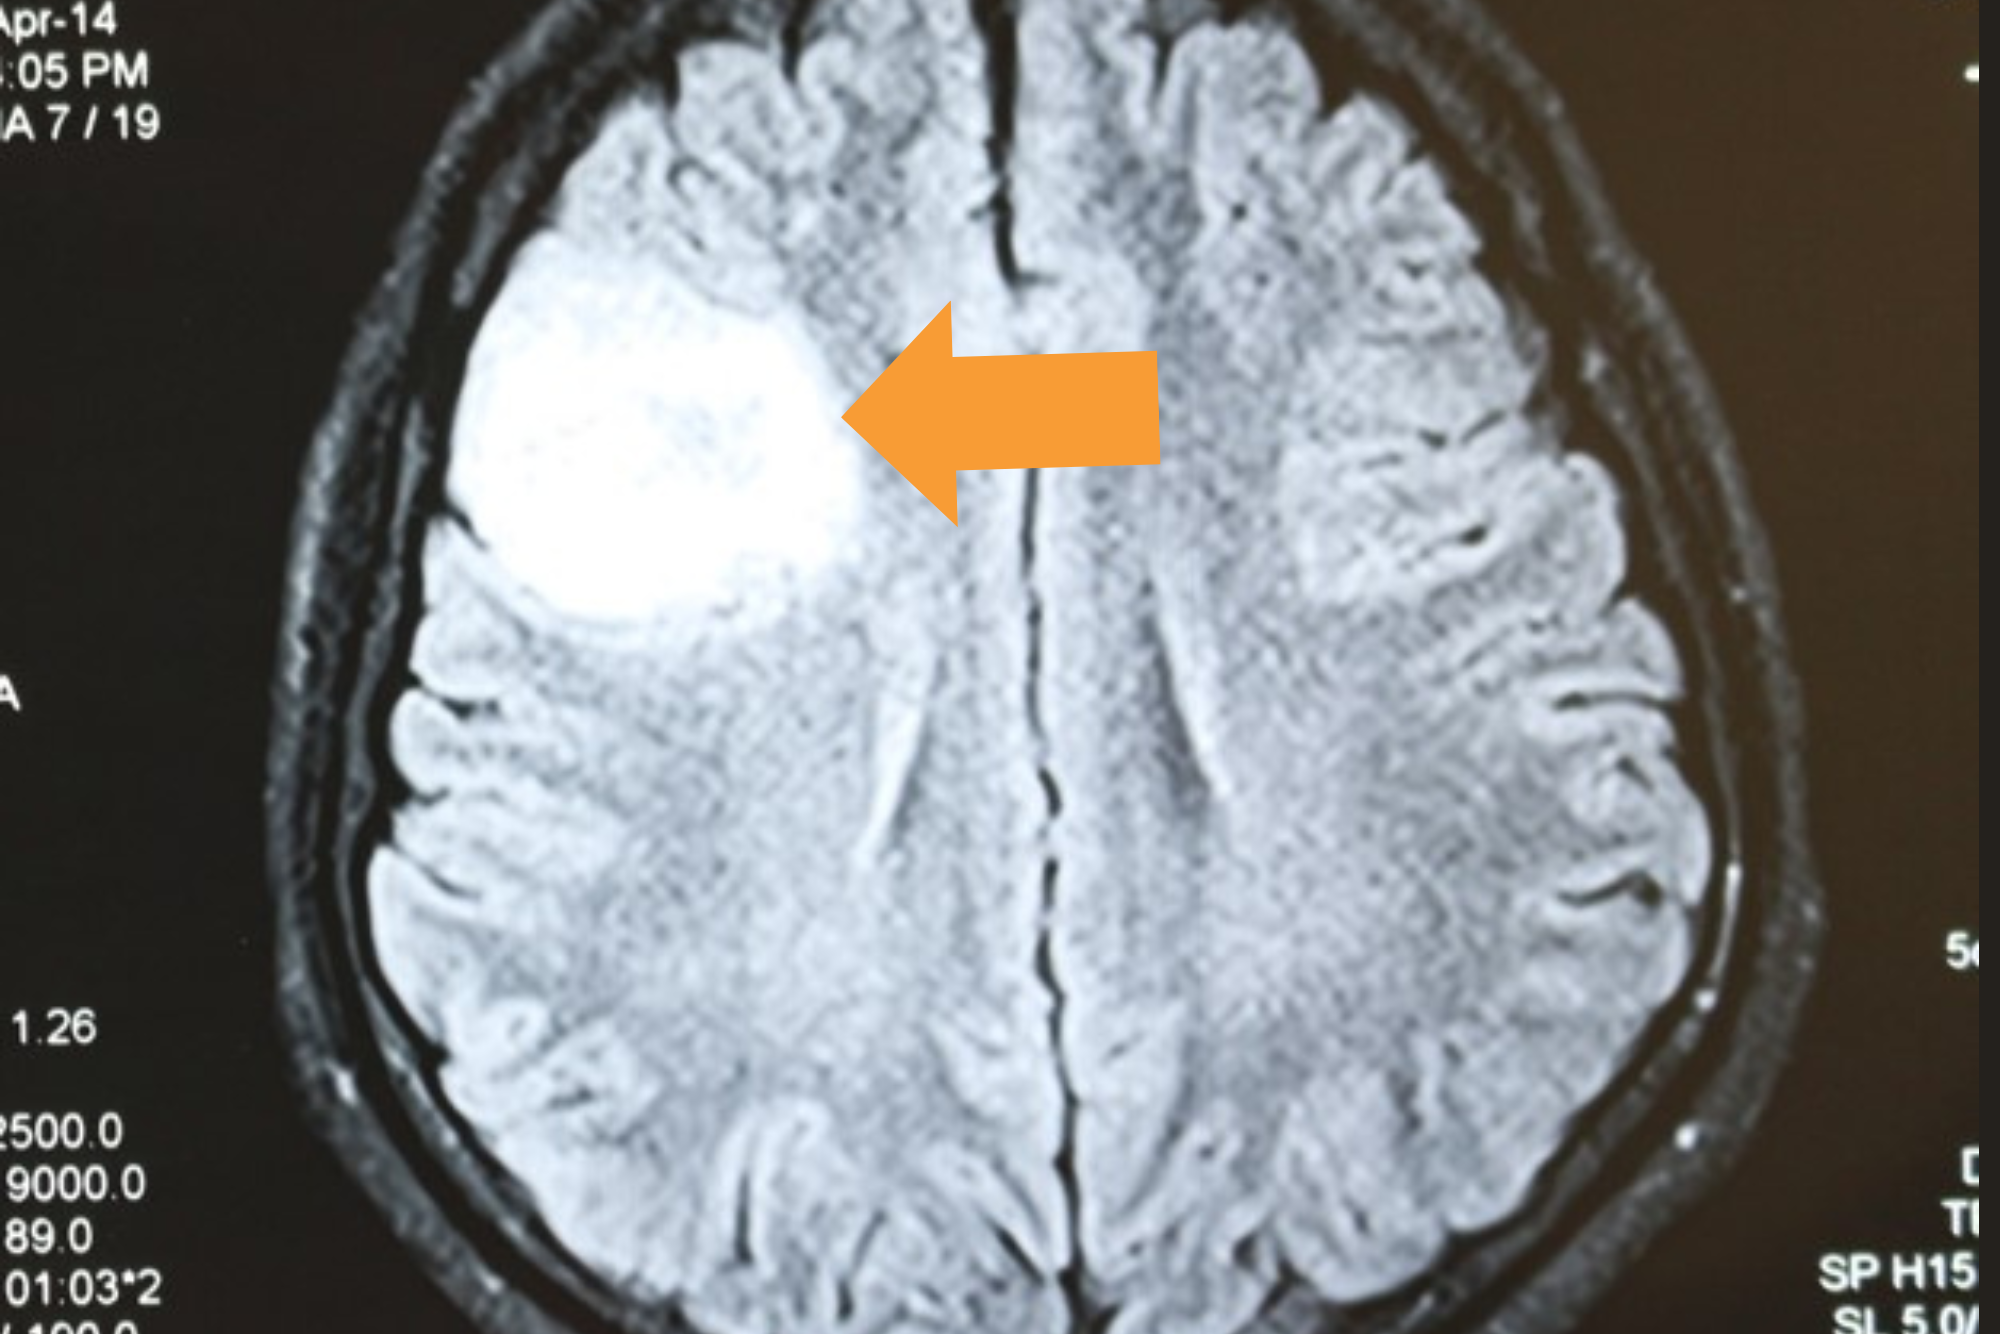

Grade II Glioma

Preoperative MRI

28 yr. Gentleman presenting with single episode of GTCS

No Neurological deficits

1 year Post operative contrast MRI